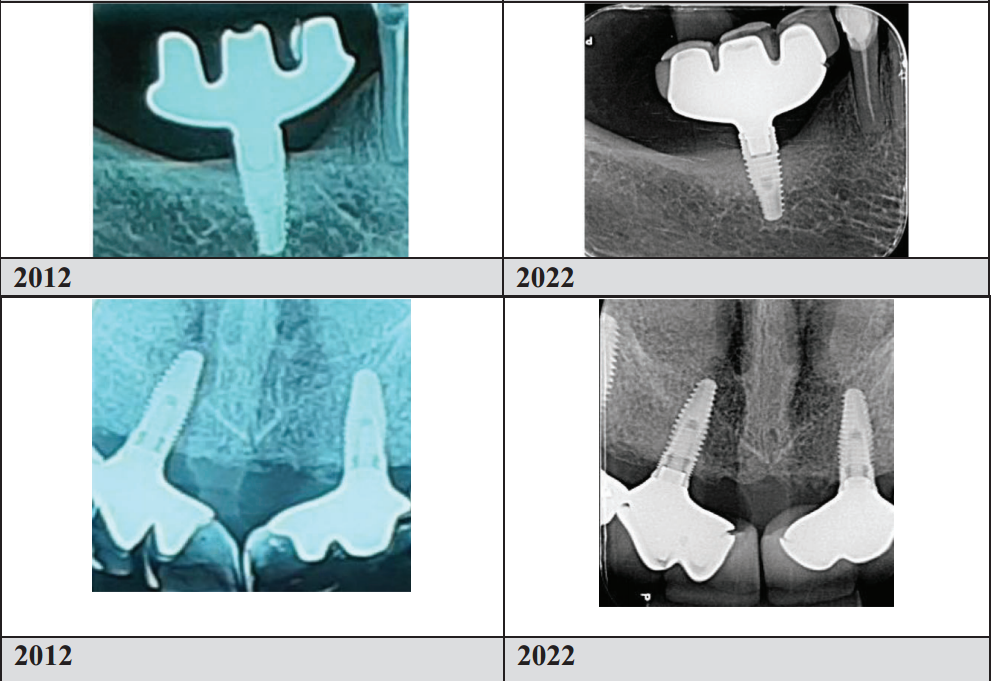

The case study published in Clinical Advances in Periodontics (2024) represents one of the most carefully documented consecutive case series in modern implant dentistry. Forty-three implants in 37 patients — non-diabetic, non-smokers, spanning both maxilla and mandible, predominantly in the posterior region — were followed for an average of 7.2 years, with the longest cases exceeding a decade.

To put the marginal bone loss figure in context: the threshold conventionally cited as compatible with peri-implant health in prospective studies is approximately 0.1–0.2 mm annually. The TA cases averaged 0.022 mm per year — a figure that not only clears the threshold but suggests the hyperbolic paraboloid geometry may actively promote bone homeostasis rather than merely tolerating it.

The radiographic panels in the published paper are equally compelling. At final examination, images show no angular bone defects, no craters, and favorable cortical thickness and trabecular mineralization — characteristics more commonly associated with pristine natural teeth than with prosthetic implant sites approaching a decade of function.

Triple Abutment 7 year follow up by Dr. Luciana and her team